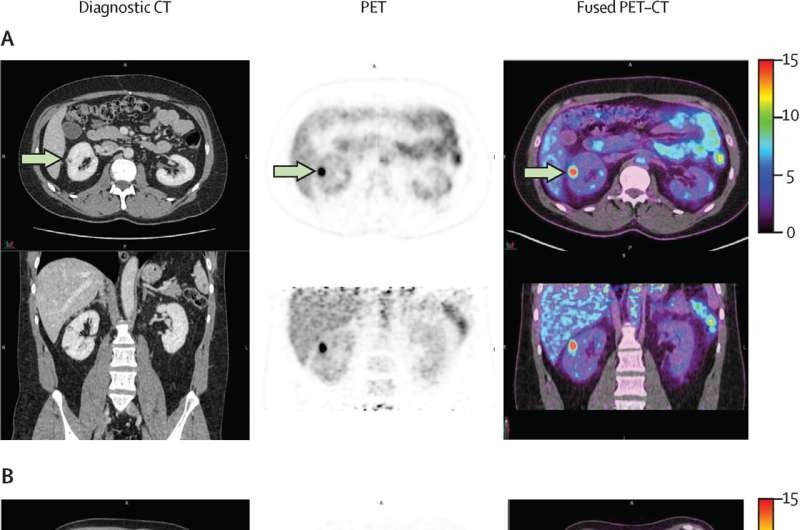

| Kỹ thuật chụp ảnh mới có thể phát hiện chính xác ung thư thận, giảm phẫu thuật không cần thiết cho bệnh nhân. (Ảnh: The Lancet Oncology 2024). |

Để giúp cải thiện việc phát hiện ung thư biểu mô tế bào thận trong, nhóm nghiên cứu đã thử nghiệm một phương pháp không xâm lấn sử dụng thuốc kháng thể đơn dòng có tên là 89Zr-TLX250, nhắm vào protein CA9 thường được tìm thấy trong ung thư biểu mô tế bào thận trong.

Phương pháp chụp ảnh mới xác định chính xác sự hiện diện của ung thư trong hầu hết các trường hợp đồng thời giảm thiểu các trường hợp dương tính giả , cho thấy hiệu suất cao với độ nhạy 85,5% và độ đặc hiệu 87,0%.